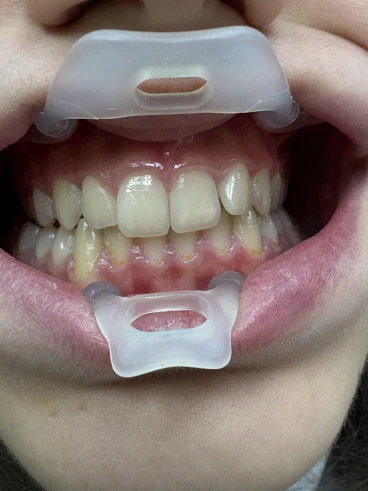

Намерете идеи за вдъхновение за Кариес и профилактика

Галерия с впечатляващи идеи за Кариес и профилактика създадени от нашите експерти. Намерете перфектната идея за Кариес и профилактика и направете своята резервация незабавно.